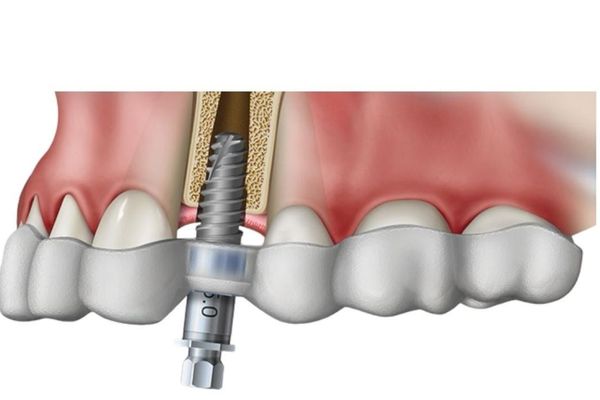

Planejamento

3D (Virtual)

O Planejamento 3D utiliza as imagens de alta resolução da Tomografia Odontológica para realizar simulações virtuais de procedimentos complexos, como a colocação de implantes dentários. O dentista consegue planejar a posição, o ângulo e o tamanho exato do implante antes mesmo da cirurgia, tudo em ambiente virtual. Este serviço garante o máximo de confiabilidade e segurança, pois permite a detecção e prevenção de possíveis complicações, como o toque em estruturas nervosas ou seios da face. É a tecnologia a serviço da excelência no resultado final do seu tratamento.

Guia

Cirúrgico

O Guia Cirúrgico é a materialização do Planejamento 3D. Trata-se de uma peça personalizada e impressa em 3D que o dentista utiliza durante a cirurgia de implantes. Ele funciona como um template que assegura a execução do procedimento exatamente como foi planejado virtualmente. Com ele, a cirurgia se torna minimamente invasiva, mais rápida e com um pós-operatório mais confortável. Na OdontoQuest, a confecção do guia é feita com materiais de alta qualidade, reforçando nosso compromisso com a inovação e o sucesso do seu tratamento.